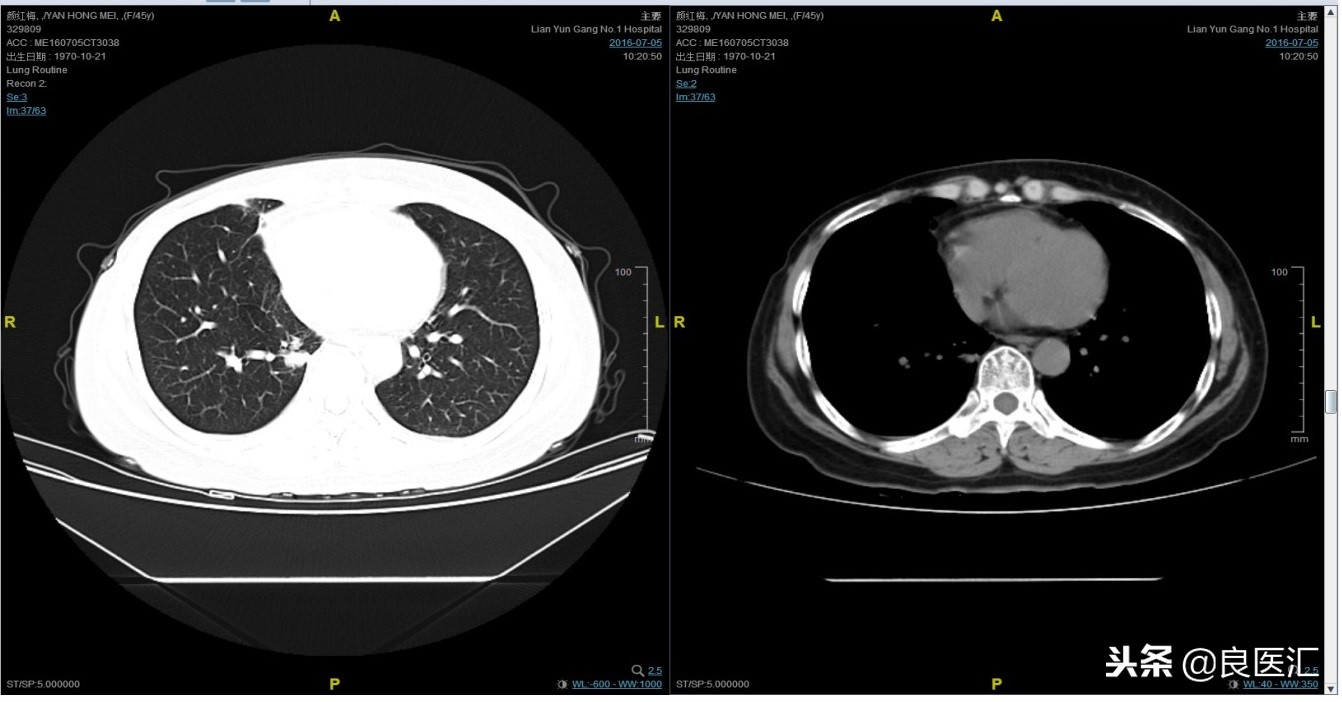

2016-7-5化疗结束后复查CT,疗效评价稳定。

患者继续曲妥珠单抗维持治疗,且自服中药。